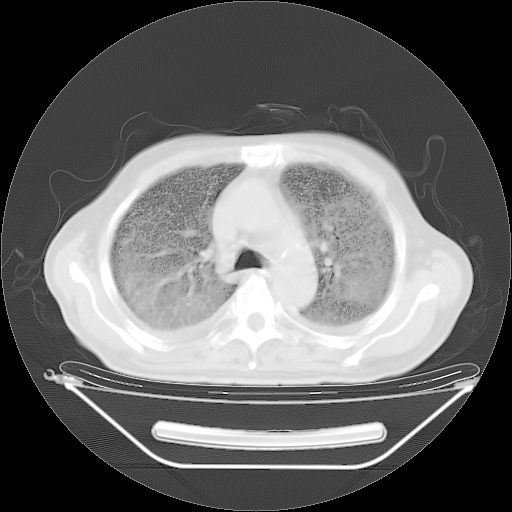

今天复查肺部CT,发现双肺广泛磨玻璃样改变。所以我把3月19日和5月9日相隔50天的肺部CT上传。请大家会诊。

5月9日肺部CT(在4月27日齐鲁医院肺部CT描述部分肺组织磨玻璃样改变,12天后肺组织广泛磨玻璃样改变)

2009年5月9日肺部CT

大致读了系列胸部CT:纵隔窗无明显异常,肺窗:从4、27至今:主要是双肺中下野外带可见毛玻璃样改变,目前处于急性肺泡炎阶段,至于原因考虑1、结替组织或胶原血管性疾病所致?2、恶性疾病如恶组在肺部所致的表现或细支气管肺泡癌?3、药物或其它原因如肺蛋白沉着症所致肺泡炎目前不太可能?总之,明天就去请我院的呼吸科、感染科、血液科和临免专家会诊哈。